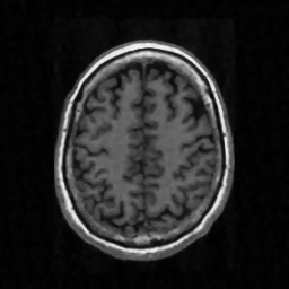

Reconstructing under-sampled k-space measurements in Compressed Sensing MRI (CS-MRI) is classically solved with regularized least-squares. Recently, deep learning has been used to amortize this optimization by training reconstruction networks on a dataset of under-sampled measurements. Here, a crucial design choice is the regularization function(s) and corresponding weight(s). In this paper, we explore a novel strategy of using a hypernetwork to generate the parameters of a separate reconstruction network as a function of the regularization weight(s), resulting in a regularization-agnostic reconstruction model. At test time, for a given under-sampled image, our model can rapidly compute reconstructions with different amounts of regularization. We analyze the variability of these reconstructions, especially in situations when the overall quality is similar. Finally, we propose and empirically demonstrate an efficient and data-driven way of maximizing reconstruction performance given limited hypernetwork capacity. Our code is publicly available at https://github.com/alanqrwang/RegAgnosticCSMRI.